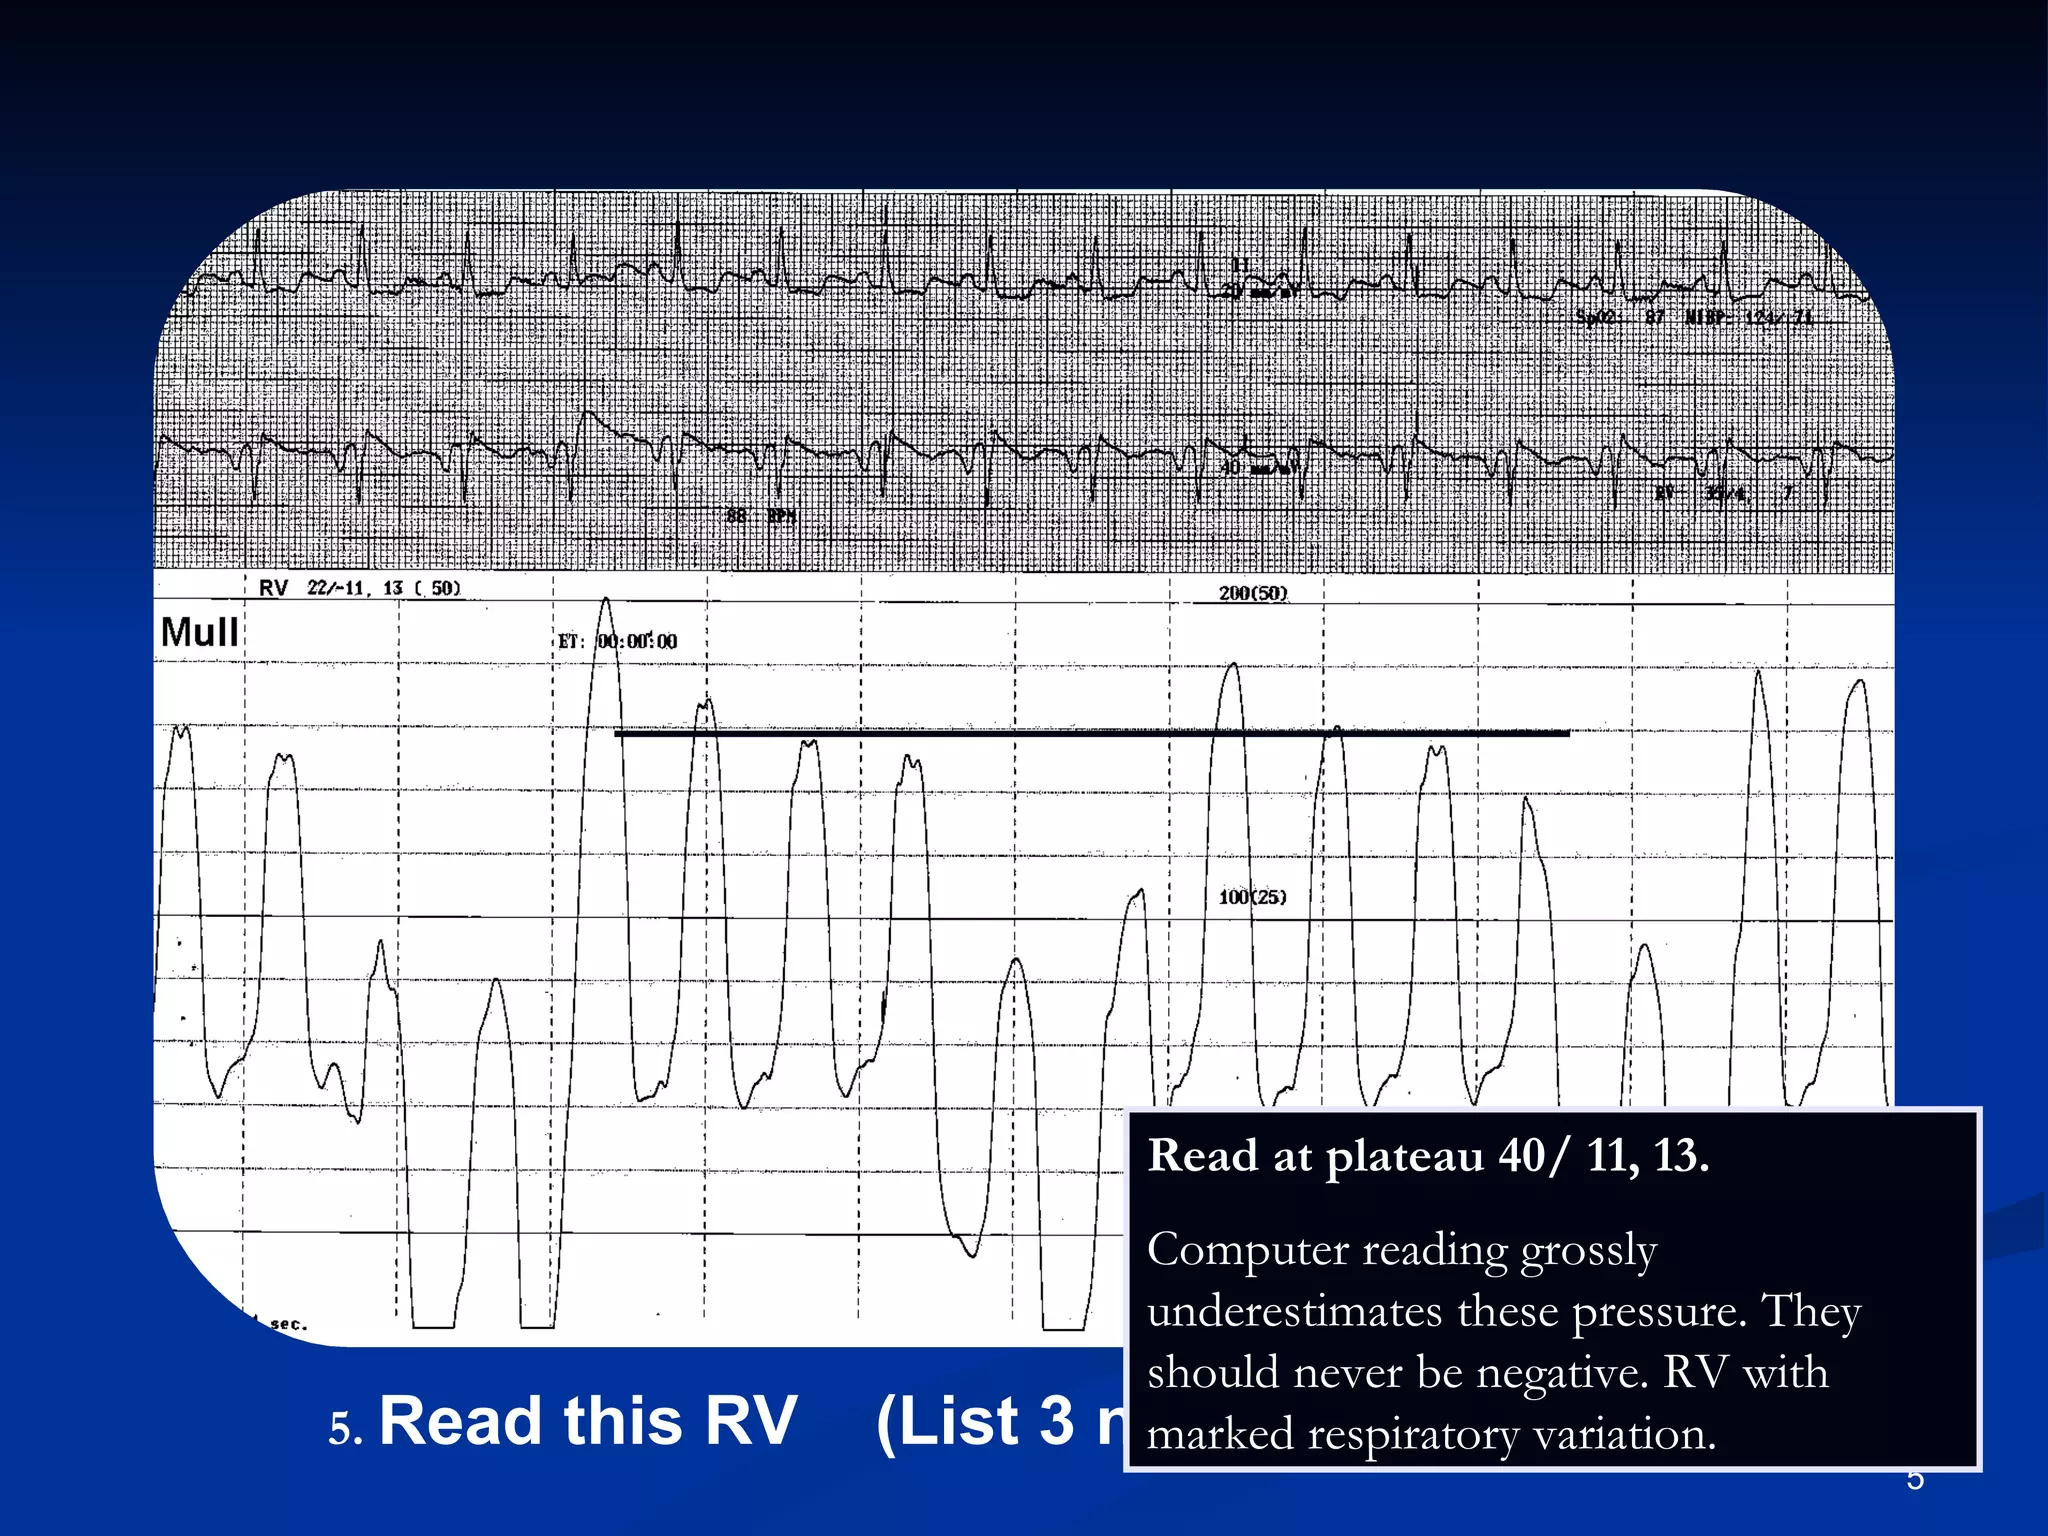

.   Read this RV  (List 3 numbers). Read at plateau 40/ 11, 13.  Computer reading grossly underestimates these pressure. They  should never be negative. RV with marked respiratory variation.